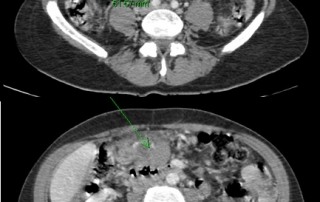

La biopsie guidée sous scanner de la masse mésentérique conduit au diagnostic de lymphome diffus à grandes cellules B CD20+ avec des zones évoquant la transformation d’un lymphome folliculaire en lymphome agressif.

Biologie : hémogramme normal, LDH augmentées à 720 UI. Biopsie médullaire et le myélogramme et l’immunophénotype médullaire montre une infiltration médullaire par un lymphome folliculaire à petites cellules, l’examen cytogénétique retrouve une translocation t(14 ;18), et l’étude en biologie moléculaire un réarrangement du gène Bcl2.

Classement LNH diffus à grandes cellules CD20+ transformation d’un lymphome folliculaire, stade IV péritonéal et médullaire, OMS = 1, LDH augmentées. L’infiltration médullaire à petites cellules caractérise la transformation du lymphome folliculaire, et n’a pas la valeur pronostique péjorative d’une infiltration médullaire d’un lymphome à grandes cellules.